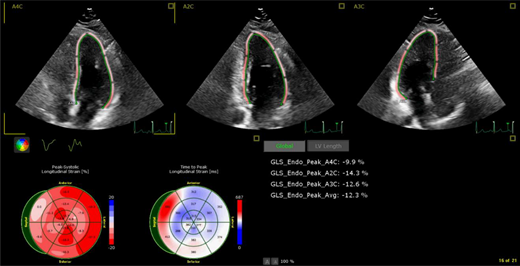

Example of borderline left ventricular systolic function (ejection fraction of 50%-55%) per 2-dimensional echocardiogram supplemented with myocardial strain measurements, which show abnormal global longitudinal strain (−12.3%) 15 years after cancer treatment. Patient was originally treated for Hodgkin lymphoma per Children's Oncology Group protocol AHOD0031 with doxorubicin, bleomycin, vincristine, etoposide, cyclophosphamide, and neck radiation.